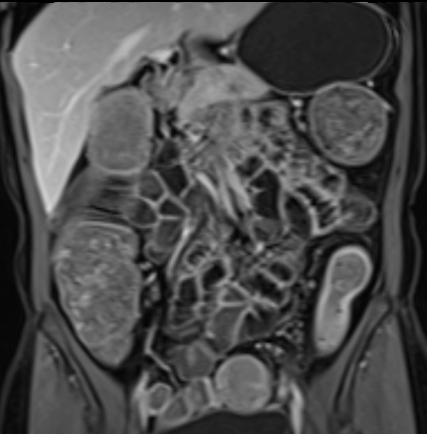

Bệnh nhân nữ 48 tuổi, đang điều trị bằng thuốc kháng TNF, được chỉ định nội soi đại tràng.

Phát hiện hẹp lòng ruột ở đại tràng sigma, không thể vượt qua được khi nội soi.

MR-enterography được thực hiện để đánh giá mức độ lan rộng của chỗ hẹp.

Cuộn qua các hình ảnh.

Ruột non bình thường, nhưng ghi nhận các đoạn hẹp ở đại tràng xuống và đại tràng ngang.

Cả hai đoạn hẹp đều có thành ruột dày đến 8 mm và ngấm thuốc rõ rệt theo kiểu niêm mạc ở đại tràng xuống và kiểu phân lớp ở đại tràng ngang.

Giãn ruột trước chỗ hẹp được ghi nhận ở cả hai đoạn.

Do các chỗ hẹp này không hiện diện khi nội soi đại tràng trước khi điều trị kháng TNF, nhiều khả năng chúng đã hình thành trong quá trình điều trị.

Do đó, quyết định phẫu thuật cắt đại tràng gần toàn bộ với miệng nối hồi-sigma đã được đưa ra.